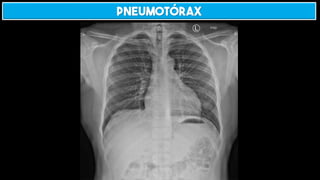

Pneumotórax